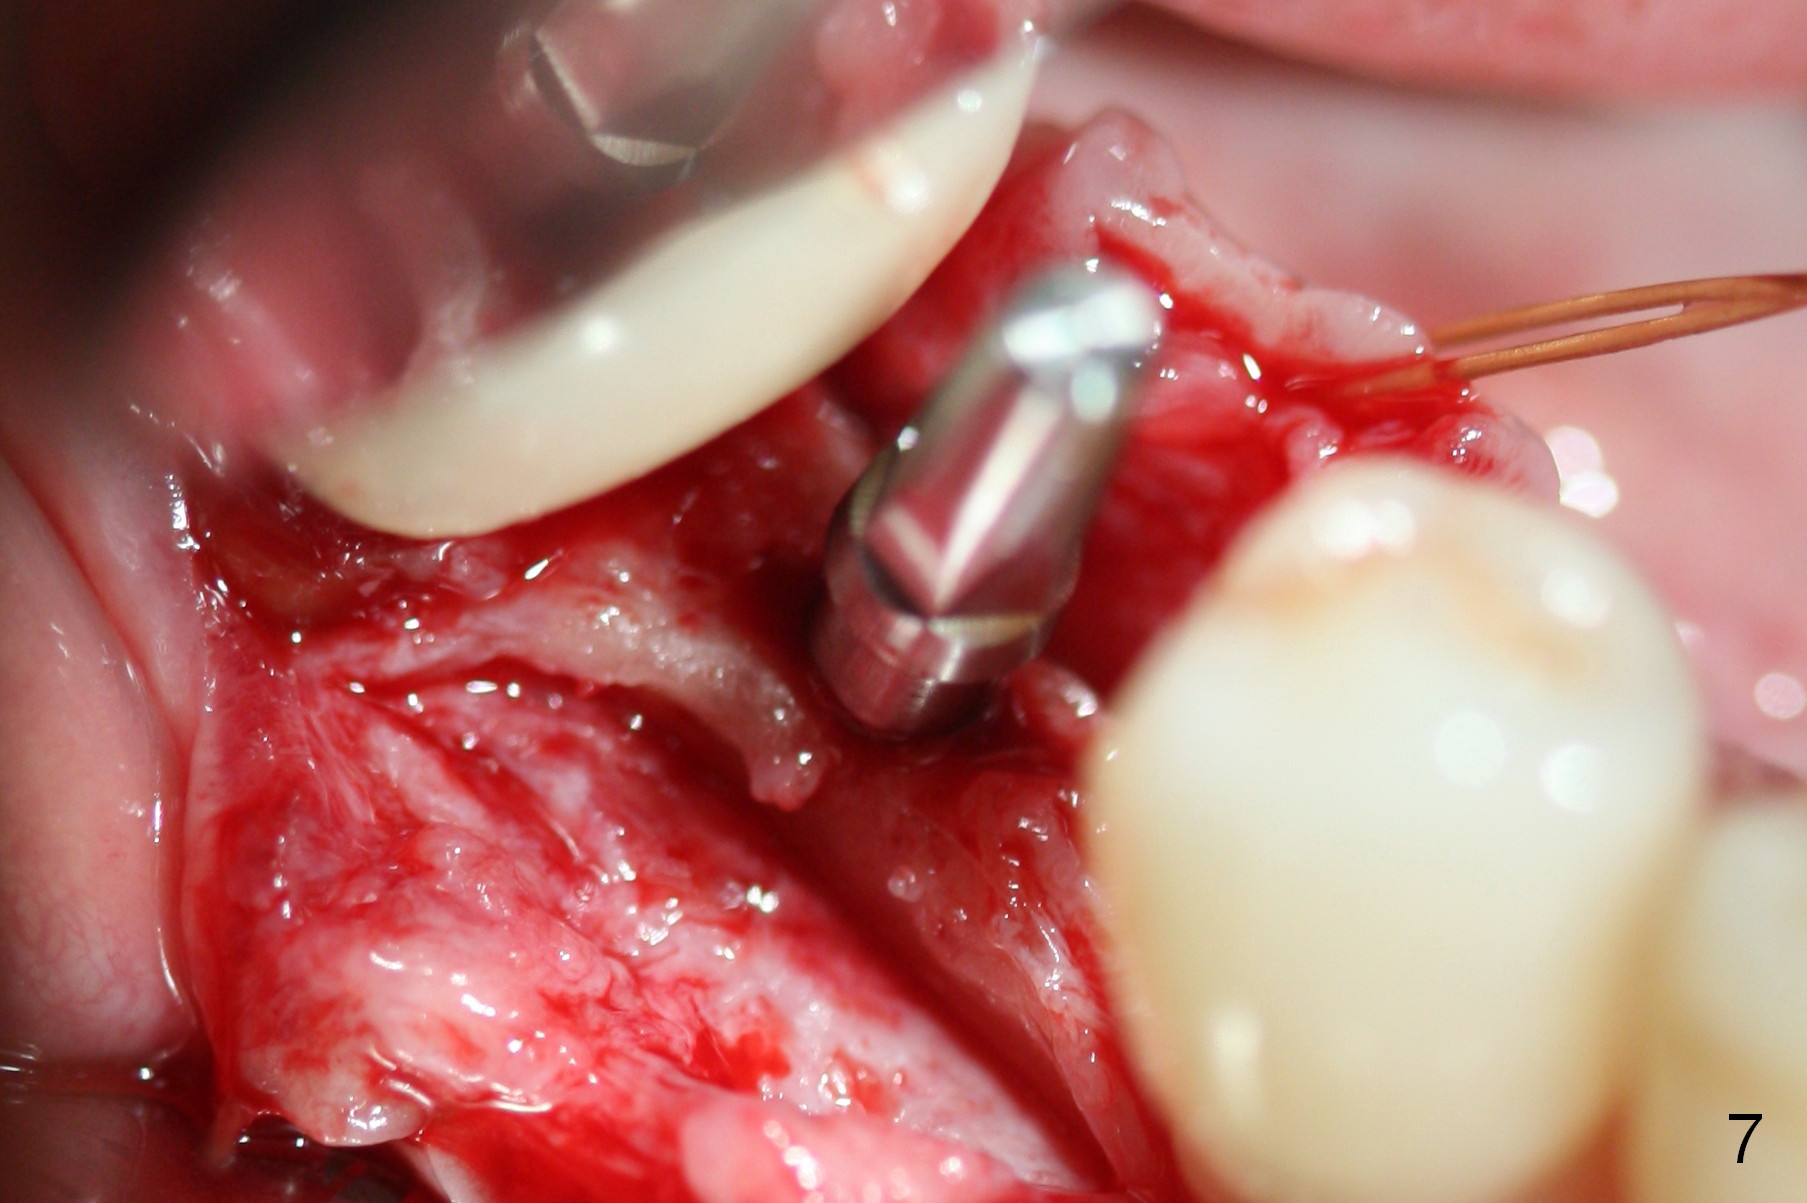

Preop photo shows the distal inclination of the tooth #28 (Fig.1).  The distal surface of the latter is reduced before incision for implant placement at #29 (Fig.2).  The buccolingual width is approximately 4 mm, as compared to 3 mm implant positioner (Fig.3).  After 1.2x10 mm osteotomy (Fig.5), the mesiodistal cortical bone is removed with a small high-speed fissural bur (Fig.4).  When a 2.5x12(2) mm 1-piece implant is placed (Fig.6), there is no buccal (Fig.7) or lingual plate perforation.  There is no postop paresthesia.  There is mild bone loss distal 4 months postop (Fig.8 *).  Take photos before and after permanent crown cementation to show increase in ridge width after bone graft and improvement in gingival health after provisional modification.  Take PA and/or BW post cementation to show that the distal bone resorption (Fig.8 *) is partially due to angulation.  No continuous bone loss 15 months post cementation (Fig.9).  There is mild bone resorption mesially 2 years 3 months post cementation (Fig.10).  The soft and hard tissues remain healthy 4 years 3 months post cementation (Fig.11,12).